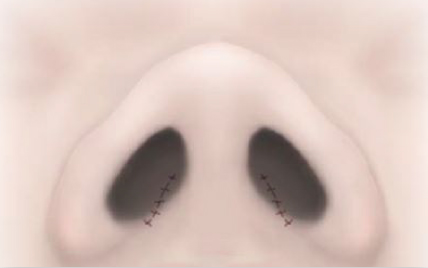

外側法は、小鼻の外側の溝に沿って余分な皮膚と組織を切除して縫合する施術です。

小鼻の丸みが取れ、面積も小さくなります。鼻翼と頬の境目となる溝に沿って傷痕ができることになりますが、この傷痕は鼻翼と頬の境目となる溝に沿ってできるため目立ちにくい特徴があります。